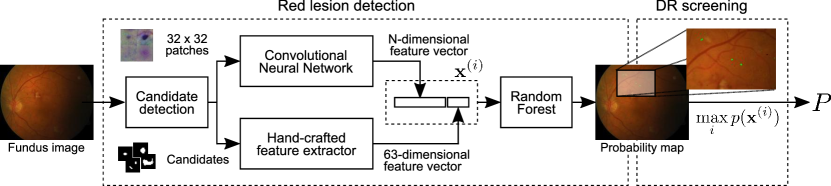

Methods: In this paper we propose a novel method for red lesion detection based on combining both deep learned and domain knowledge. Features learned by a convolutional neural network (CNN) are augmented by incorporating hand crafted features. Such ensemble vector of descriptors is used afterwards to identify true lesion candidates using a Random Forest classifier.

In this study we propose to take advantage of both deep learned and manual engineered features for red lesion detection in fundus photographs. In particular, we propose to learn a first set of discriminative features using a light CNN architecture, and then augment their original characterization ability by incorporating hand crafted descriptors. These ensemble vectors of features are used to train a Random Forest classifier that is applied at test time to discriminate between true and false lesion candidates. We experimentally observed that the deep learned features are complementary to the manually engineered, and are aided by the incorporation of domain knowledge.

In this paper we propose to learn discriminative models for red lesion detection by combining both deep learned and hand crafted features. First, an unsupervised, candidate detection approach based on morphological operations is applied to retrieve a set of potential lesions. Next, a CNN is trained from a set of patches around the candidate lesions to learn a first feature vector. These descriptors are augmented with a set of hand crafted features to improve their ability to distinguish the true positive lesions. A Random Forest (RF) classifier is trained using this hybrid feature vector, and is then applied for refining the set of candidates, discriminating between true lesions and false positives. We empirically observed that combining both sources of information improved performance not only when evaluating our method on a per-lesion basis but also when analyzing its potential for DR screening or need for referral detection on an image-level basis. Our results on benchmark data sets such as e-ophtha (Decencière et al., 2013), DIARETDB1 (Kauppi et al., 2007) and MESSIDOR (Decencière et al., 2014) show that our strategy outperforms other state of the art methods that are not only based on red lesion detection but also in detecting other pathological structures such as exudates or neovascularizations. An extensive analysis of the complementarity of the deep learned features with respect to the hand crafted ones is also provided, with the purpose of assessing their contribution in the discrimination process.

A schematic representation of our method is depicted in Figure 2. Lesion candidates retrieved with morphological operations (Section 2.1) are filtered using a set of hybrid descriptors. Regular patches centered on each candidate connected component are collected to build a training set that is used to train a CNN (Section 2.2). A 63-dimensional vector of hand crafted features (Section 2.3) is also computed per each of the candidates. A Random Forest (RF) classifier (Section 2.4) is afterwards trained on the resulting combination of features, and used to classify the new candidates. Since the presence of red lesions is the first indicator of DR, the maximum over lesion likelihoods is used to assign a DR probability, as done by Seoud et al. (2016) and Antal and Hajdu (2012).